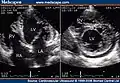

Trabeculation of the ventricles is normal, as are prominent, discrete muscular bundles greater than 2mm. In non-compaction there are excessively prominent trabeculations. Echocardiography is the reference standard for diagnosing NCC, although it can be well defined by computer tomography scan, positron emission tomography and magnetic resonance imaging.[13] Chin, et al., described echocardiographic method to distinguish non-compaction from normal trabeculation. They described a ratio of the distance from the trough and peak, of the trabeculations, to the epicardial surface.[14] Non-compaction is diagnosed when the trabeculations are more than twice the thickness of the underlying ventricular wall.

Transthoracic two-dimensional echocardiogram in apical four chamber and parasternal short axis at the level of both ventricles demonstrate dilatation, deep trabeculae and intertrabecular recesses in the inferior, lateral, anterior walls, middle and apical portions of the septum and apex of the left ventricle.